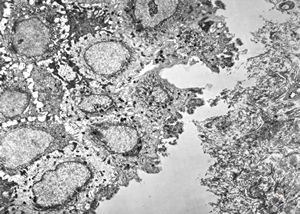

F, 1y. | epidermolysis bullosa … dystrophic form